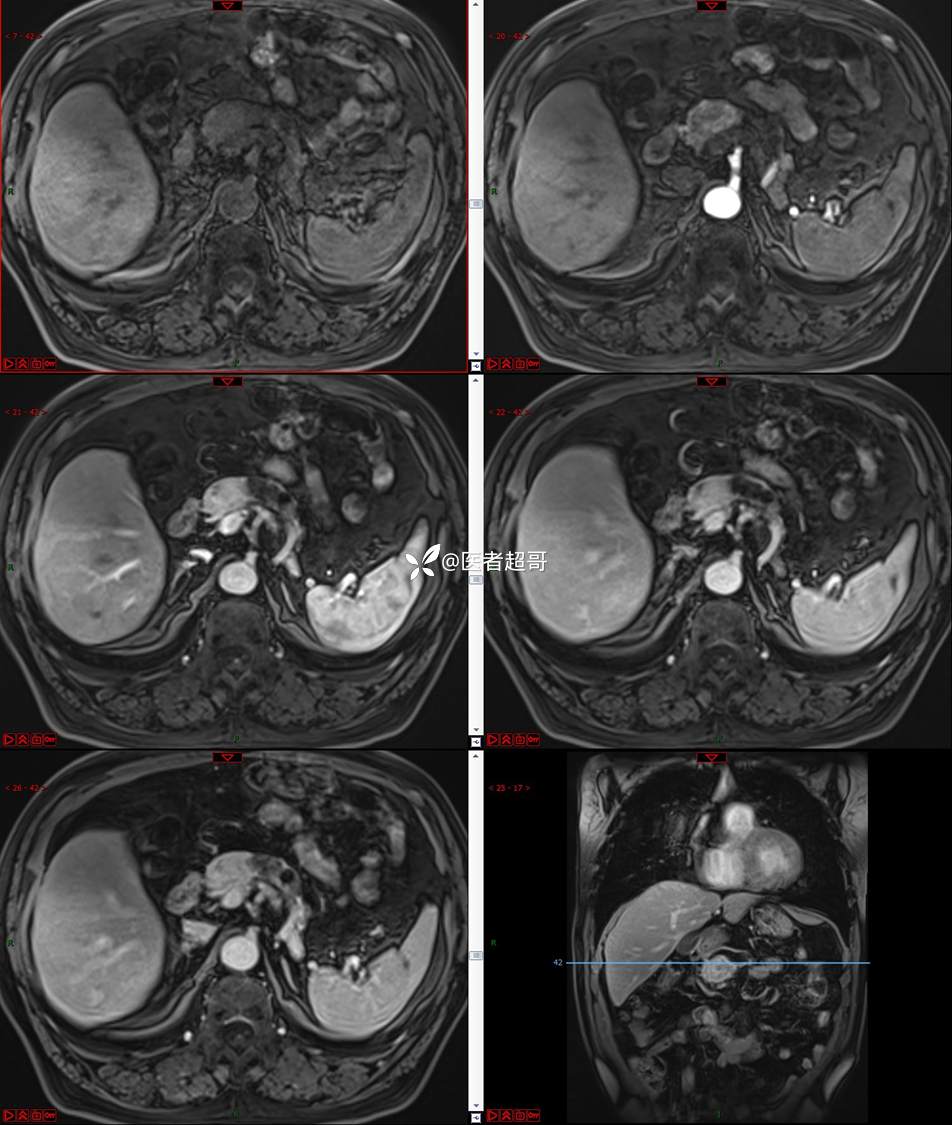

【影诊笔记677】查体发现胰腺占位性病变1周,细节决定成败,请诊断分析!

主 诉:查体发现胰腺占位性病变1周。

现病史:患者1周前在当地查体时发现胰腺占位性病变,无恶心、呕吐,无腹痛,无寒战、高热,无咳嗽、咳痰等异常不适,来我院门诊查上腹部CT平扫+强化:胰腺尾部异常密度灶。今为求进一步治疗,门诊以“胰腺占位性病变”收入院。患者自发病以来,一般情况可,神志清,精神可,普通饮食,二便正常,体重及体力无明显改变。